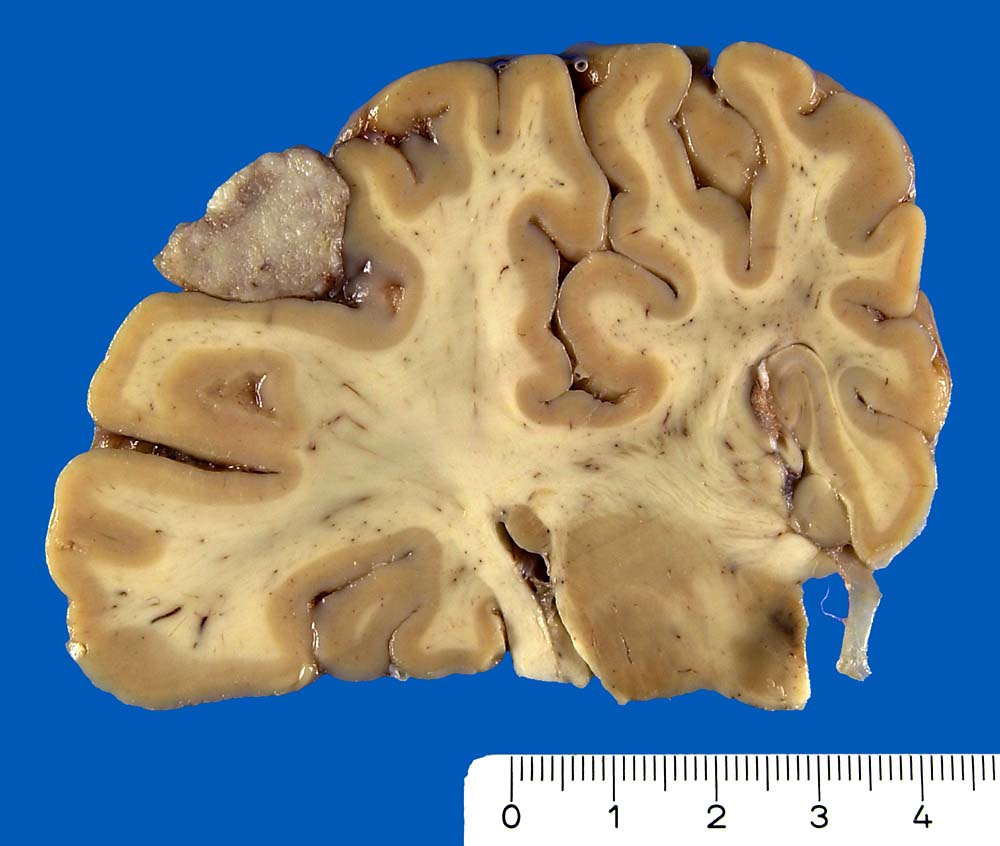

Die meisten Meningeome sind gutartig und fallen in die Kategorie WHO Grad I. Atypische Meningeome (WHO Grad II) machen zwischen 4.7-7.2% aller Fälle aus, anaplastische Menigeome (WHO Grad III) sind noch seltener. Meningeome sind oft multipel bei Patienten mit hereditärer Prädisposition und bei Neurofibromatose 2 sowie bei 10% der sporadischen Fälle. Meist wachsen Meningeome langsam. Sie sind in der Regel scharf begrenzt und sitzen der Dura breitbasig auf. Das Einwachsen von Meningeomgewebe in die Dura mater und/oder die benachbarte Schädelkalotte ist noch kein Malignitätszeichen und noch durchaus vereinbar mit einem benignen Meningeom WHO Grad I. Demgegenüber ist das Einwachsen in das benachbarte Hirnparenchym in aller Regel atypischen oder anaplastischen Meningeomen vorbehalten. Die Konsistenz ist prall-elastisch oder fest und das Tumorgewebe kann fokal verkalkt sein. Das Meningeom en plaque bedeckt flächenhaft die Dura als dünne Platte.

• Der Dura breitbasig aufsitzender scharf begrenzter halbkugeliger Tumor.